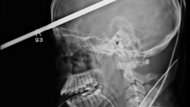

What’s the Big Idea? A Florida teenager will have a bad headache for a while after being shot through the head with a three-foot fishing spear, but doctors expect a […]